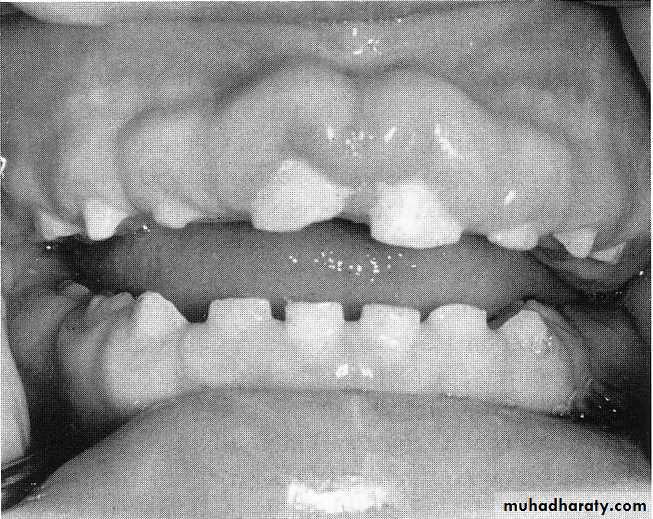

Hereditary gingival fibromatosis (HGF) is characterized by a slow, progressive, benign enlargement of the gingivausually has an autosomal dominant mode of inheritance .

elephantiasis gingivae or hereditary hyperplasia of the gums.

The gingival tissues appear normal at birth but begin to enlarge with the eruption of the primary teeth.

continue to enlarge with eruption of the permanent teeth until the tissues essentially cover the clinical crowns of the teeth

Dense fibrous tissue often causes displacement of the teeth and malocclusion

The condition is not painful until the tissue enlarges to the extent that it partially covers the occlusal surface of the molars and becomes traumatized during mastication.Treatment: Surgical removal of the hyperplastic tissue

can recur within a few months after the surgical procedure